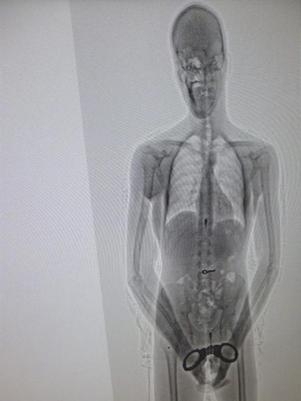

Preso engole chave para abrir algemas, mas é pego por scanner

Uma imagem de scanner permitiu a autoridades penitenciárias do Uruguai descobrir que um preso que estava sendo transferido carregava em seu estômago algumas chaves que seriam usadas para ele mesmo fugir ou vendê-las dentro da prisão, informaram nesta terça-feira fontes oficiais